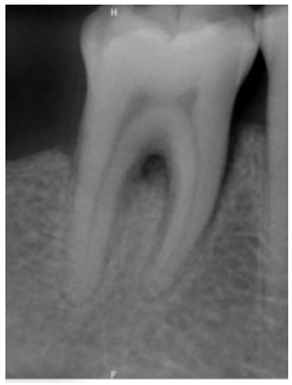

| Original Images | Gaussian High-Pass Filter | Gaussian High-Pass Filter + Mask | |

|---|---|---|---|

| Validation Accuracy | 84.16% | 87.21% | 94.97% |

| Validation Loss | 0.7634 | 0.4578 | 0.1822 |

| Image | ![]() | ![]() | ![]() |